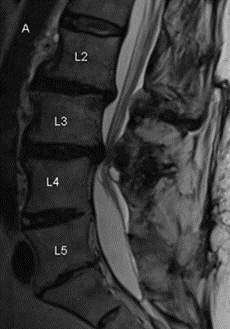

De klachten van een lumbale kanaalstenose worden veroorzaakt door een vernauwing van het onderste gedeelte van het wervelkanaal. Deze vernauwing is vaak het gevolg van artrose (slijtage van de gewrichten binnen de wervelkolom). Artrose is een normaal verouderingsverschijnsel dat bij iedereen in meer of mindere mate optreedt. Als reactie op artrose verdikken de wervels en de bindweefselbanden van de wervelkolom. Bij slijtage/afplatting van de tussenwervelschijven kunnen deze gaan uitpuilen in het wervelkanaal. Al deze veranderingen gaan ten koste van de wijdte van het wervelkanaal (zie figuur 1 en 2). Daardoor blijft er minder ruimte over voor de zenuwwortels die vanuit het wervelkanaal/de rug naar de benen lopen.

Een MRI scan van de onderrug kan aantonen of er ook daadwerkelijk sprake is van een abnormale vernauwing van het wervelkanaal. Bij patiënten die geen MRI scan kunnen ondergaan, bijvoorbeeld omdat zij een pacemaker hebben, is het maken van een CT scan (met contrastmiddel) een goed alternatief.

MRI’s met een vernauwing van het wervelkanaal (”umbale stenose’)